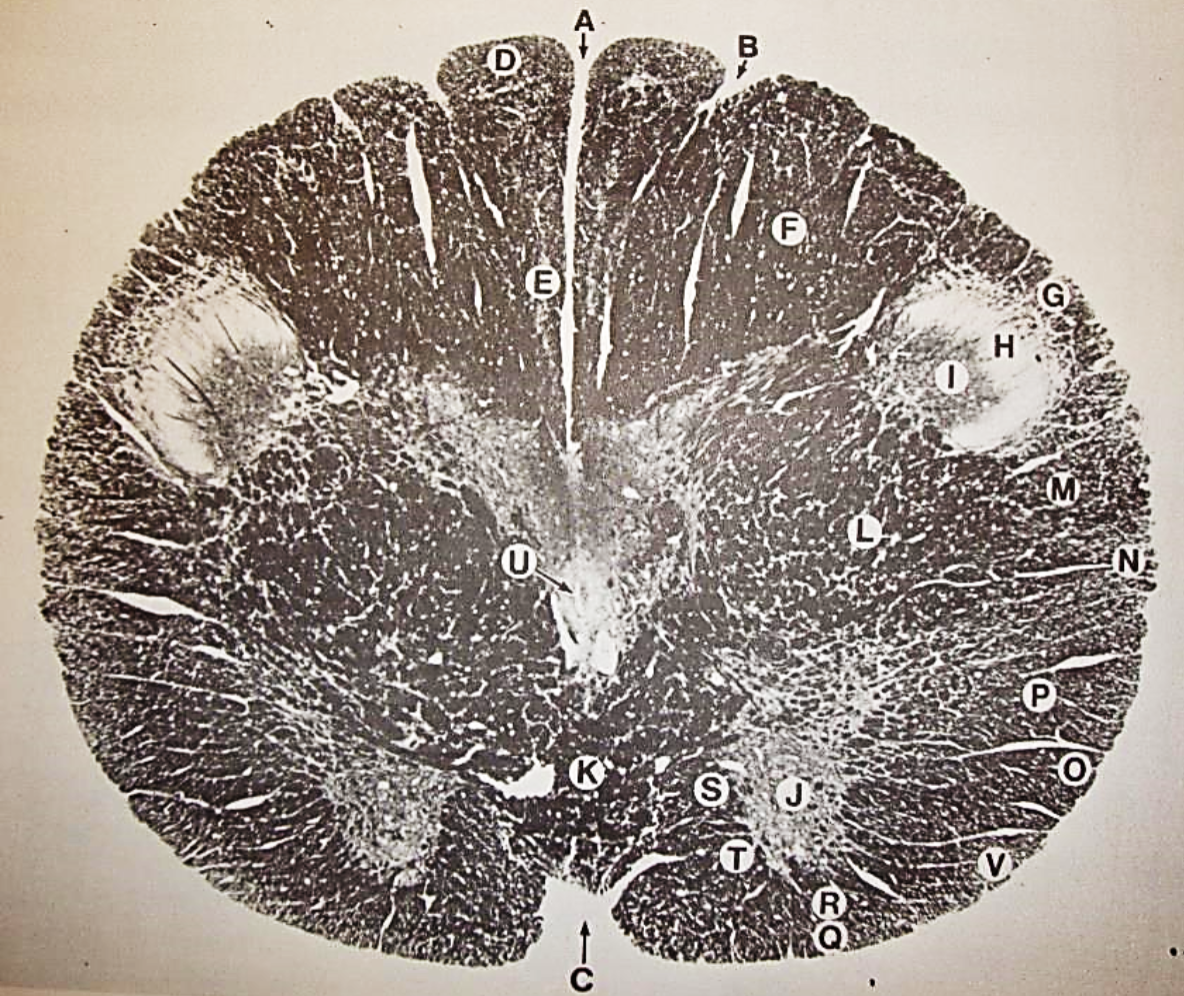

A

posterior median sulcus

B

posterior intermediate sulcus

C

anterior median fissure

D

gracile fasciculus

E

Gracile nucleus

F

fasciculus cuneatus

G

spinal trigeminal tract

H+I collectively

spinal trigeminal nucleus

J

Accessory nucleus

K

pyramidal decussation

L

lateral corticospinal tract

M

rubrospinal tract

N

posterior spinocerebellar tract

O

anterior spinocerebellar tract

P

lateral spinothalamic tract

Q

anterior spinothalamic tract

R

lateral vestibulospinal tract

S

medial longitudinal fasciculus

T

tectospinal tract

U

central canal